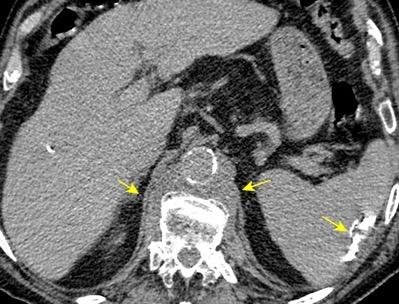

T. mixto de células

Ganglios retroperitoneales (flechas negras)

germinales del testículo izquierdo Nódulos pulmonares múltiples. (flechas verdes). Ganglios paratraqueales. (flechas amarillas). Dudoso ensanchamiento retrocrural (flechas negras)

Panda A et al. “Straddling Across Boundaries”. Thoracoabdominal Lesions: Spectrum and Pattern Approach. Curr Probl Diagn Radiol, 2015